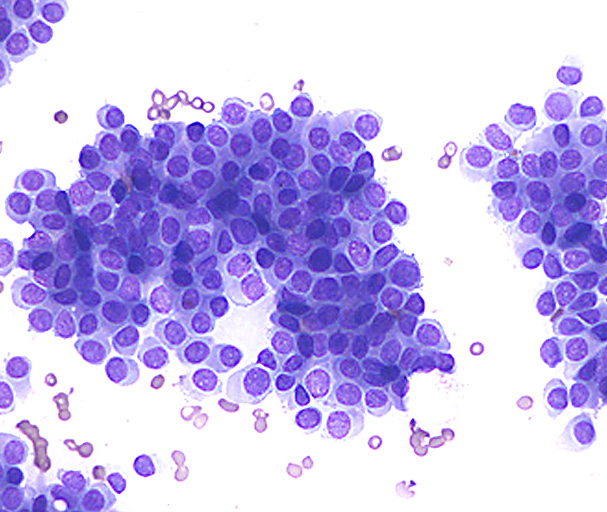

Classic LCIS - microscopic images

As shown below, LCIS is characterized by a lobulocentric proliferation of cells that expand lobular units. The LCIS cells are uniform, loosely cohesive and evenly spaced (“marbles in a bag”). They are slightly larger than normal breast epithelial cells, with indistinct cell borders and pale cytoplasm. Two types may coexist. Type A LCIS cells have small to slightly enlarged, uniform, round nuclei with inconspicuous nucleoli. Type B cells have larger nuclei, more abundant cytoplasm and more prominent nucleoli.

Normal breast cells appear to transform to LCIS based on changes to the E-cadherin gene (mutations, loss of the wild type allele or methylation). E-cadherin mediates intracellular adhesion and cell polarity and plays a key role in maintaining lobular architecture; it can also inhibit the growth and invasion of breast cancer cells. Loss of E-cadherin protein (which occurs in > 95% of cases), or rarely its aberrant expression (due to mutations or loss of the wild type allele), results in loss of cell to cell cohesion, increased cell proliferation and altered organization of the lobules, giving rise to the characteristic microscopic appearance of lobular carcinoma in situ.

Classic LCIS is usually an incidental finding in a breast biopsy performed for other indications, including screening detected calcifications or mass producing lesions. The calcifications are frequently produced by columnar cell lesions, a low risk lesion. LCIS lesions are frequently found as multiple foci within the same (70%) or both breasts (20 - 60%).

LCIS is a risk factor for subsequent breast cancer: women with LCIS have a 7 - 10 fold increase in breast cancer risk, an absolute risk of 1 - 2% per year and a lifetime risk of 30 - 40%. The time from LCIS diagnosis to cancer ranges from 15 to 30 years.

Classic LCIS is typically treated conservatively with active surveillance and anti estrogens. Unlike DCIS, it is no longer considered a malignant condition. If diagnosed incidentally, excision is not recommended because the risk of finding invasive carcinoma on excision is very low (< 5%). Excision is recommended only if other high risk proliferative lesions are found or there is discordance between histology and imaging (i.e. the microscopic findings are different from what is expected from the imaging, suggesting the lesion was missed).